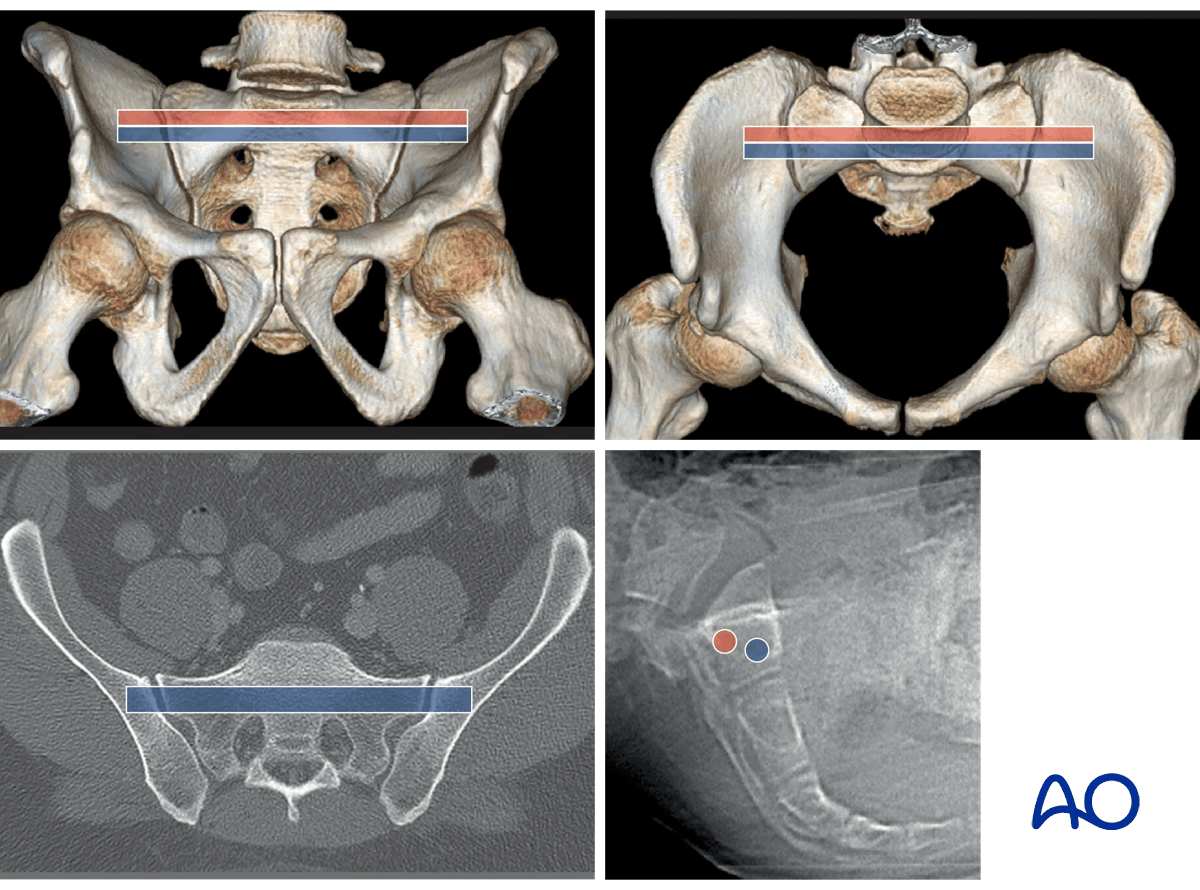

For fixation of sacral fractures in a nondysmorphic pelvis, an ISS can be placed in the blue channel.

A second screw can be added, through the smaller (posterior) red channel, to increase fixation stability.

A third screw, if required, may be placed transversely through a channel in the upper anterior second sacral body.

These images illustrate the channel for an S2 transsacral screw in a normal pelvis.

In this dysmorphic pelvis, the red channel is placed through an adequate S2 segment, rather than the dysmorphic first segment.

Upper left - Outlet: the pathway is slightly cranial to the second sacral neural foramina.

Upper right – Inlet: the 2nd sacral segment lacks the anterior indentations of the 1st .The anterior cortical surface of the 2nd is visible below the indentations of the 1st

(If upper sacral segment (oblique) screws are also desired, they should be inserted before the second segment transsacral screw, since the latter screw prevents visualization of the upper segment anterior alar indentations, which are the anterior limit to upper segment screw placement)